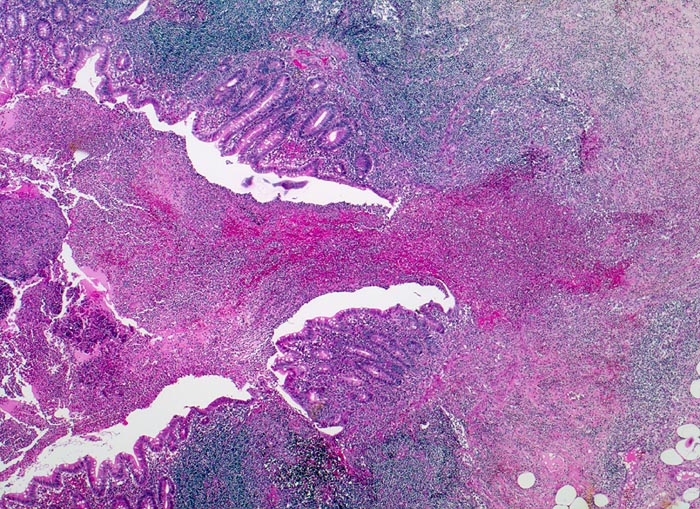

PathoPic ID 3430 - akute eitrige ulzerophlegmonöse Appendizitis: Ulkus

akute eitrige ulzerophlegmonöse Appendizitis: Ulkus

Entzündung / Reparatur

Appendix vermiformis

Darm, Anus

Rechts im Bild ein Ulkus. Daneben erhaltene Kolonmukosa. Die Appendixwand ist diffus entzündlich infiltriert.

Seit 6 Stunden Schmerzen im Unterbauch rechts mit zunehmender lokaler Druckempfindlichkeit. Übelkeit.

Histologie

25